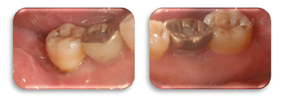

术后6个月,47远中及颊侧中央PD 4~5 mm,BI1,颊侧中央出现附着龈,退缩根面得到覆盖(图15,图16)。

术后1年,47远中及颊侧中央PD 3~5 mm,BI1,颊侧中央根面得到覆盖,X线片示47远中骨缺损明显修复,患者的咬合不适基本得到缓解(图17,图18,图19)。

术后2年,47牙龈无明显红肿,远中及颊侧中央PD 3~4 mm,BI1,颊侧中央附着龈宽约2 mm,颊侧中央根面无退缩,患者的咬合无不适(图20,图21)。

术后4.5年,47牙龈无明显红肿,远中及颊侧中央PD 3~4 mm,BI1,颊侧中央附着龈宽约2 mm,X线片示远中骨高度保持稳定(图22,图23,图24)。

术后6年,47牙龈无明显红肿,远中及颊侧中央PD 3~4 mm,颊侧退缩根面得到覆盖,颊侧中央出现附着龈,宽约2 mm,BI1,X线片示远中骨缺损明显修复(图25,图26,图27),CBCT示47颊侧骨缺损深约4 mm,宽约1.5 mm,远中骨缺损深约5 mm,宽约3 mm,较初诊时颊侧及远中骨缺损均得到明显修复且骨高度保持稳定(图28,图29)。